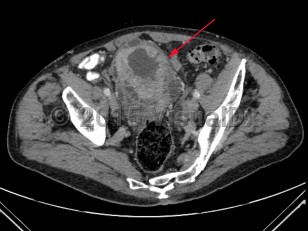

Imaging Studies image of Bladder cancer - imageId=7885454. Click to open in gallery.  caption: '<span>Axial image from an enhanced CT scan of the pelvis  demonstrating marked irregular wall thickening of the bladder.</span>'

Axial image from an enhanced CT scan of the pelvis demonstrating marked irregular wall thickening of the bladder.